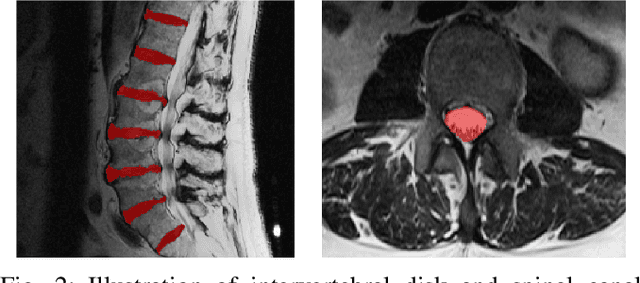

Abstract:Yes, it can. Data augmentation is perhaps the oldest preprocessing step in computer vision literature. Almost every computer vision model trained on imaging data uses some form of augmentation. In this paper, we use the inter-vertebral disk segmentation task alongside a deep residual U-Net as the learning model, to explore the effectiveness of augmentation. In the extreme, we observed that a model trained on patches extracted from just one scan, with each patch augmented 50 times; achieved a Dice score of 0.73 in a validation set of 40 cases. Qualitative evaluation indicated a clinically usable segmentation algorithm, which appropriately segments regions of interest, alongside limited false positive specks. When the initial patches are extracted from nine scans the average Dice coefficient jumps to 0.86 and most of the false positives disappear. While this still falls short of state-of-the-art deep learning based segmentation of discs reported in literature, qualitative examination reveals that it does yield segmentation, which can be amended by expert clinicians with minimal effort to generate additional data for training improved deep models. Extreme augmentation of training data, should thus be construed as a strategy for training deep learning based algorithms, when very little manually annotated data is available to work with. Models trained with extreme augmentation can then be used to accelerate the generation of manually labelled data. Hence, we show that extreme augmentation can be a valuable tool in addressing scaling up small imaging data sets to address medical image segmentation tasks.